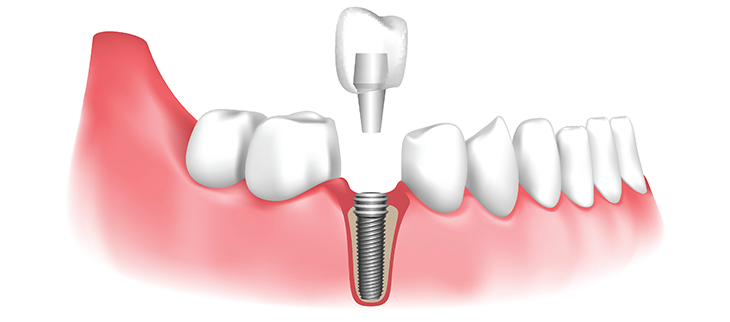

Dental Implant is a more advanced form of replacement for tooth/teeth. It is a screw like an object which acts as the root of the tooth, normally made up of titanium metal or ceramic material.

The dental implant is placed into the jaw bone using a minor surgical procedure.

Parts of a Dental Implant:

A dental implant is made up of three parts

1. Artificial root (dental implant screw)

2. Artificial tooth/teeth

3. Extension piece (connects both implant and tooth)